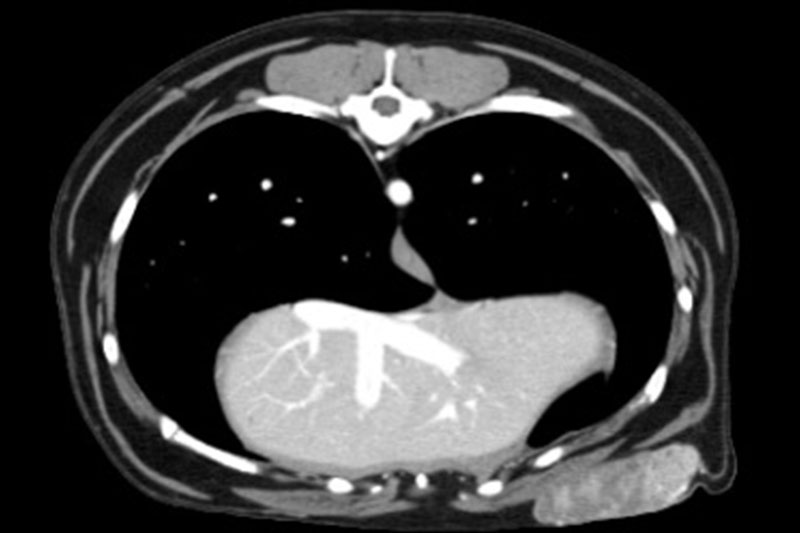

| 흉부(가슴) | 폐종양, 늑골 골절, 기관지 협착, 심장 주변 병변 등 |

폐 질환의 상세 평가